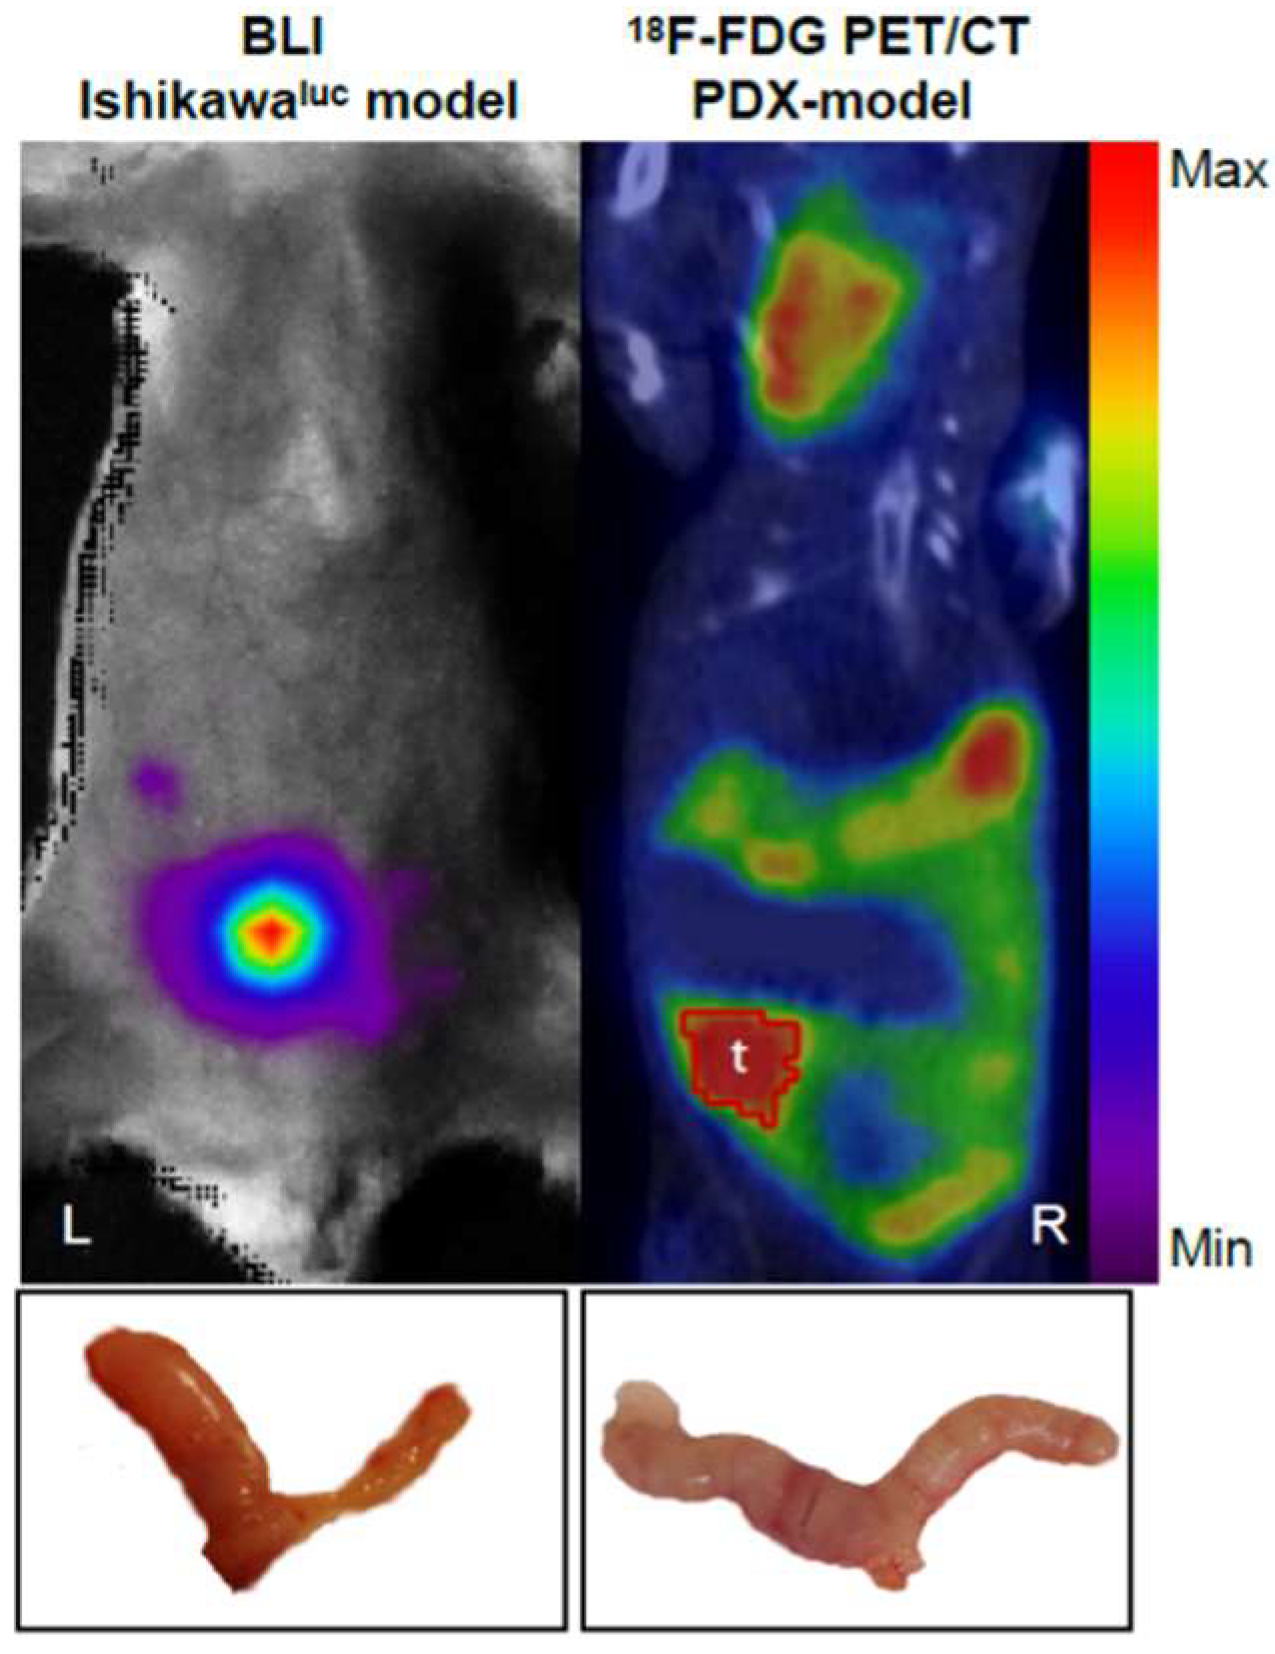

2.2. Strategies for EC PDX Model Monitoring

- Positron emission tomography (PET) is a highly sensitive and specific imaging technique used to visualize the distribution and concentration of radiolabelled molecules injected into murine models. It is a form of quantitative whole-body imaging used for the in vivo monitoring of biological processes, such as enzymatic reactions, cellular metabolism, and cell proliferation and migration [41], which makes it an ideal tool for the imaging of cancer [32,42].

- Whole-body optical imaging is a sensitive technique based on fluorochromes excitation by an external light source (fluorescence) or by chemiluminescent enzymatic light emission reactions within the animal (bioluminescence). Despite the poor spatial resolution due to light scattering, this technique enables the integration of the light signal emitted to obtain a 2D planar image. Green fluorescence protein (GFP) has been widely used to measure in vivo tumour growth as well as the effect of metastatic spread and drug treatments on different types of cancer in mouse models [50,51].